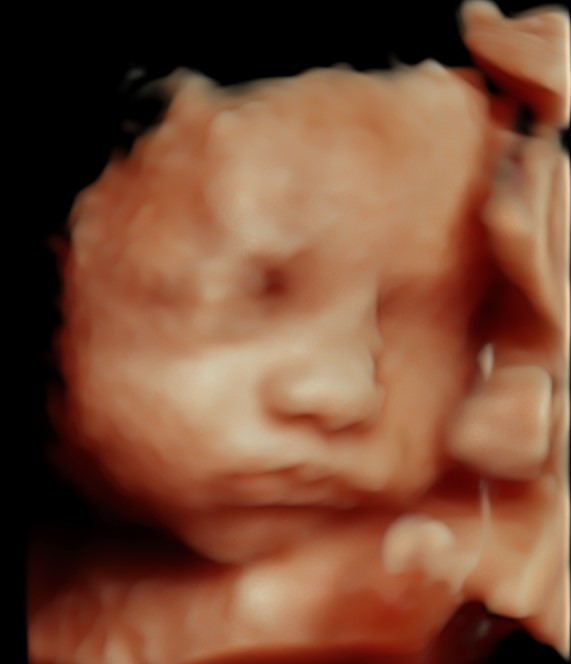

4D/5D/HD Ultrasound Gallery

Gallery